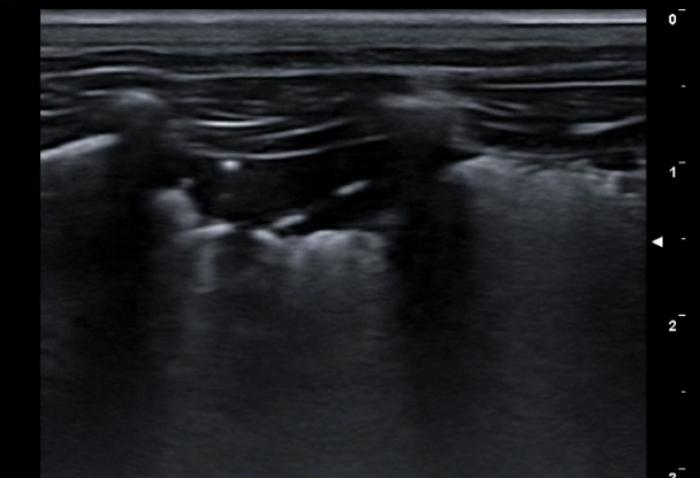

Signo del sinusoide y cuadrilátero

La presencia de pequeñas colecciones de fluido en el espacio pleural no siempre son del todo fáciles de evaluar, especialmente si el contenido en cuestión es lo suficientemente celular como para no visualizarse anecoico. El uso del modo M en estas circunstancias puede ser muy útil. Nos posicionamos con el transductor transversal en el espacio intercostal seleccionado (áreas más declives tienen mayor porcentaje de éxito puesto que el fluido desciende por gravedad), situamos el cursor y activamos el modo M, puesto que el pulmón no está en contacto en todo momento con la pared costal, la LP dibujará un movimiento sinusoidal en el registro en movimiento, muy diferente de la recta hiperecogénica que vemos en el tórax sano (Figura 9A-B).

Por contra, en modo B es posible visualizar lo que se llama signo del cuadrilátero, que es el área comprendida entre la pared costal (límite superior), costillas (laterales) y pleura visceral (límite inferior) dejando un aspecto poligonal en el foco con fluido (Figura 10A-B).